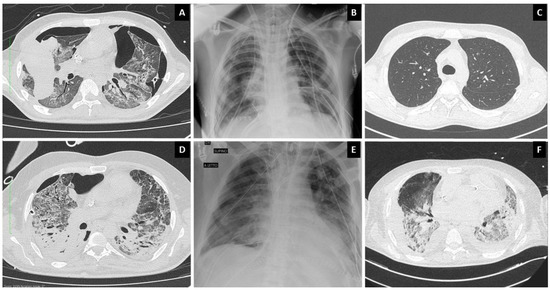

2. Presentation of Cases